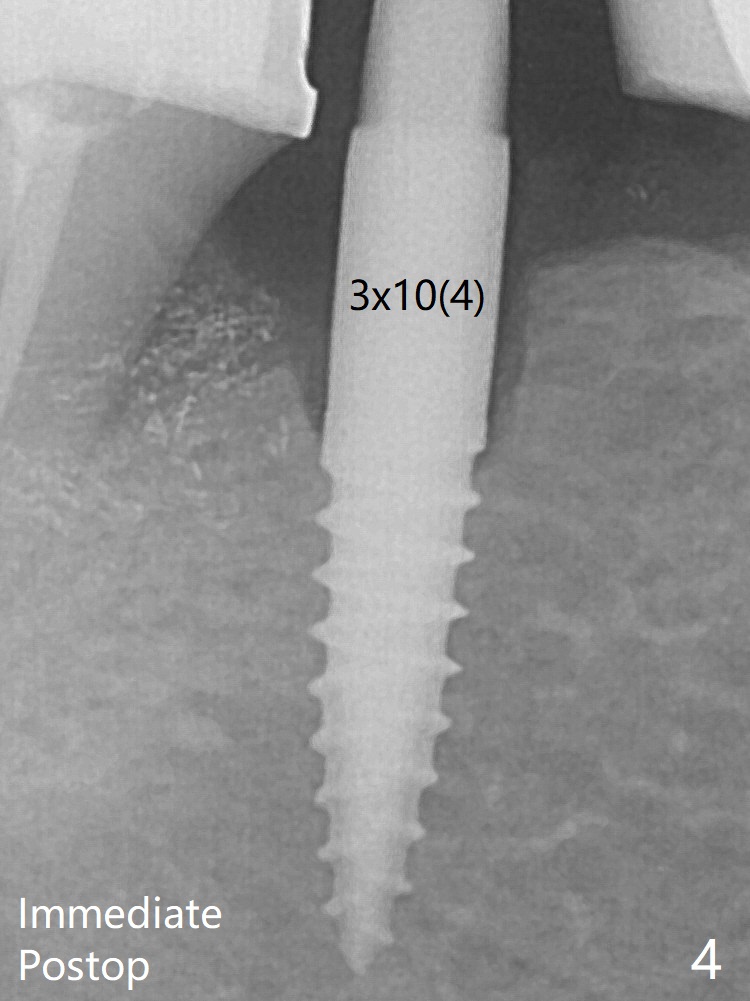

In fact the crown at #30 is redone because of loose proximal contact with #31; there is no bone resorption 13 months post cementation (Fig.11). The crestal bone loss is observed 3 months postop (Fig.6 arrowheads), as related to ridge reduction (cortical bone). Since then, there has been no bone resorption.